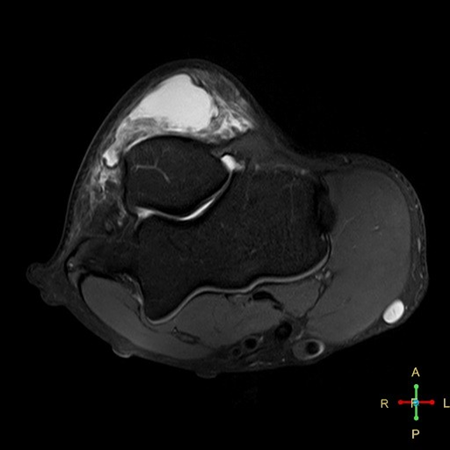

Axial PDw SPAIR